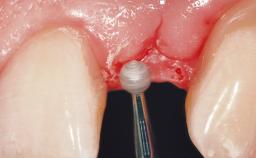

Immediate Placement of an Implant in a Maxillary Right Central Incisor Site

A 30-year-old female patient was referred to the office for the treatment of tooth 11. Her chief concern at the initial visit was to inquire, “Why is my tooth pink?” Upon clinical examination, it was determined that tooth 11 had a previous history of trauma and that the clinical crown had become noticeably pink in color as a result of internal resorption. This diagnosis was confirmed radiographically, indicating a large radiolucency involving the central and distal portions of the clinical crown. It was determined that restoration of this tooth was not possible, and that extraction was indicated. The presence of a mid-line diastema, which the patient wanted to reproduce, directed the treatment plan for tooth replacement utilizing a dental implant.